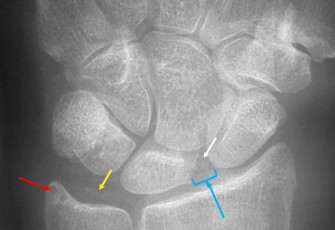

Son diagnostic n’est pas toujours aisé, en particulier dans les formes chroniques qui peuvent en imposer pour une arthrose ou une polyarthrite rhumatoïde. Le diagnostic est confirmé par la mise en évidence des cristaux de PPC dans le liquide synovial, sinon orienté par les données de l’imagerie, l’échographie étant l’examen le plus sensible.

- La chondrocalcinose articulaire asymptomatique. La découverte de la pathologie est le plus souvent fortuite, à l'occasion d'une radiographie de l'articulation : les dépôts de cristaux de pyrophosphate de calcium ne sont responsables d'aucun symptôme. Cette forme est plus courante chez les personnes âgées.